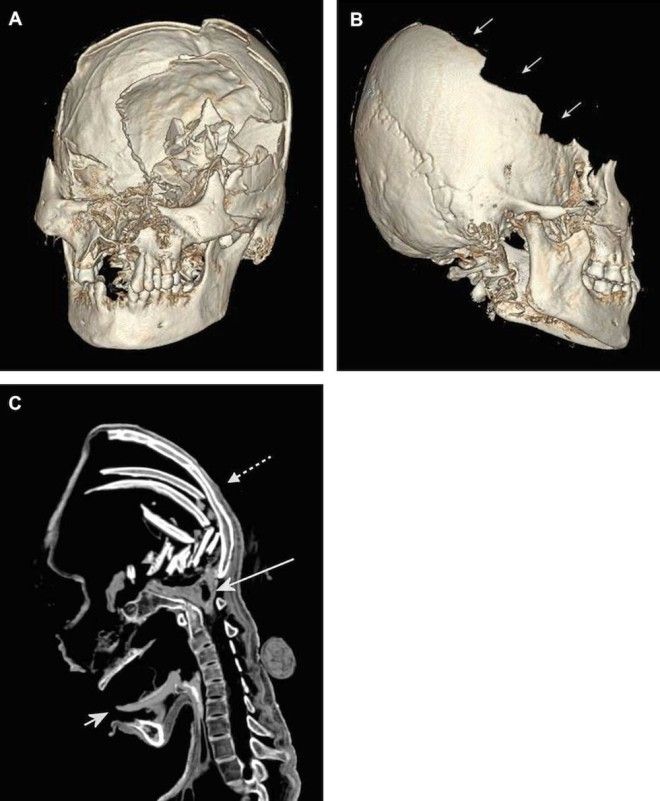

14. С одной стороны лицо мумии выглядело вполне нормальным, но внутри ее черепные кости были разбиты.

15. Как видите, передняя часть ее черепа полностью размозжена.